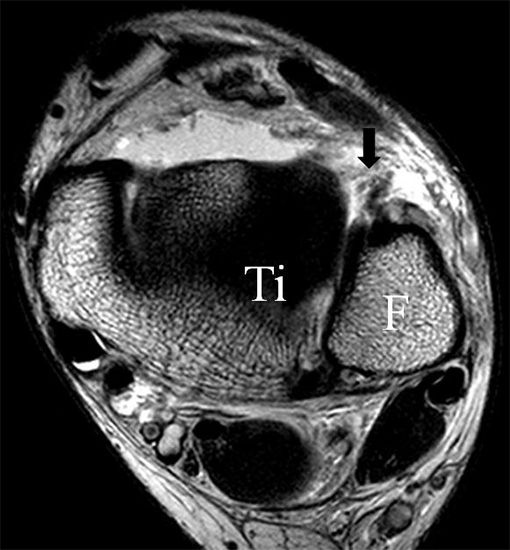

Die Kombination aus 3 Tesla Hochfeldtechnik und/oder Verwendung hochauflösender Spulen (Empfangseinheiten des Signals) erhöht die Signalausbeute. Dies erlaubt mit akzeptablen Messzeiten (3-4 Minuten pro Sequenz) im Routinebetrieb eine Darstellung mit einer Schichtdicke von 1-2 mm und einer Ortsauflösung von 0,2 x 0,2 mm in der Schichtebene in den anatomisch am besten zeichnenden 2D Turbospinechosequenzen. Der Unterschied der diagnostischen Wertigkeit zwischen einer kernspintomographischen „Standarduntersuchung“ und einer HR-MRT wird besonders in der chondralen Diagnostik sichtbar (Abb. 1 a-c). Unter Verwendung von 3D Sequenzen, die jedoch entscheidende Schwächen bei der Darstellung der Ligamente aufweisen, werden sogar Schichtdicken weit im Submillimeterbreich erreicht. Eine weitere Erörterung der Sequenz spezifischen Eigenheiten soll jedoch an dieser Stelle unterbleiben.

Jedoch findet man sich auch hier mit dem Problem der in den Standard-Projektionen schräg verlaufenden Syndesmose konfrontiert. Der oligofaszikuläre Aspekt der vorderen Syndesmose kann in der axialen Schnittebene eine zum Verwechseln ähnliche Morphologie wie eine Ruptur aufweisen (Abb. 15 b und c). Doppelangulierte Schnitte entlang der Achse (schräg koronar/schräg sagittal) lassen hingegen eine eindeutige Beurteilung der Bandstrukturen zu (Abb. 16) und verbessern die Syndesmosendiagnostik.

Bezogen auf die Transversalebene verläuft die Syndesmose ca. 30° schräg cranio-caudal anguliert (Abb. 15 a). Häufig lassen sich drei Hauptfaszikel differenzieren: das kürzeste superiore, das stärkste mittlere und das längste kaudale Faserbündel. Ein akzessorisches Bündel, das anteriore-inferiore, tibiofibulare Ligament (AITFL) oder auch Bassett-Ligament wird in 80-94% der Patienten nachgewiesen 8. Dies weist einen unmittelbaren Bezug zur anterolateralen Talusschulter auf (Abb. 17). In Kombination mit einer Außenbandinstabilität und konsekutivem, talarem Vorschub kann dieses zu einem Impingement an der anterolateralen Taluskante führen mit nachfolgender chondraler oder osteochondraler Läsion.